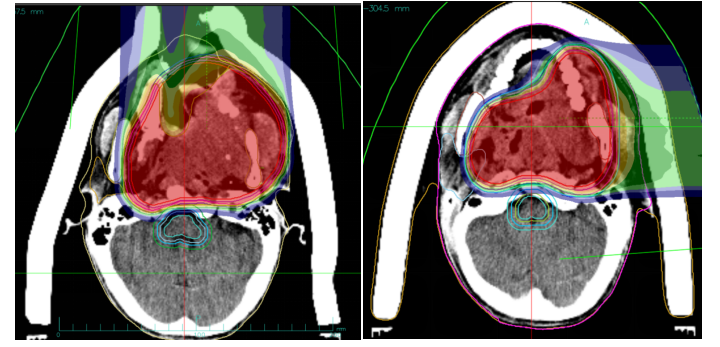

1. **Target Delineation:**

- GTV: MRI-indicated irregular nodules and masses in the left nasal cavity, nasopharynx, oropharynx, left maxillofacial region, periorbital area, and nasal root, including surrounding invaded tissues. A 0.5 cm margin was added to form PTVboost.

- CTV: High-risk areas based on GTV, with appropriate cropping in the right eye and right optic nerve. A 0.3 cm margin was added to form PTV1.

- GTVnd_R: Enlarged lymph nodes in the right neck level II.

- GTVnd_L: Enlarged lymph nodes in the left neck levels Ib and II.

- CTVnd_R: Lymph node drainage area in the right neck level II.

- CTVnd_L: Lymph node drainage area in the left neck levels Ib-II.

A 0.3 cm margin was added to form PTVnd_R and PTVnd_L.

2. **Prescription Dose:**

- PTVboost: 8 Gy(RBE)/2 fractions

- PTV1, PTVnd_R, PTVnd_L: 64 Gy(RBE)/16 fractions

- Total dose to the tumor area: 72 Gy(RBE)/18 fractions

Figure 1: The total dose to the tumor region reached 72 Gy (RBE).

Figure 2: PTVnd_L 64 Gy (RBE)/16 fx.

Figure 3: PTVnd_R 64 Gy (RBE)/16 fx, with the total dose to the tumor region reaching 72 Gy (RBE).